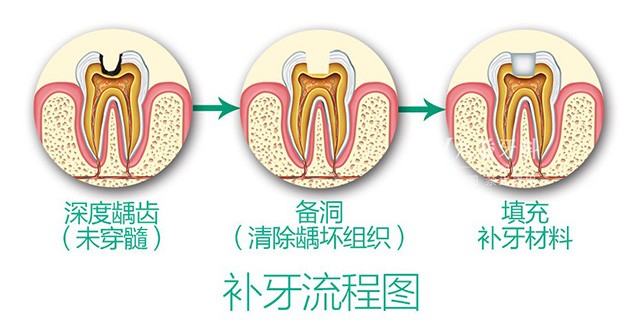

牙齿蛀牙、缺损和缺失,不但容易产生口腔问题,而且也为生活带来了不便。补牙很好的为大家解决了牙齿烦恼。补牙是用人造物质修补牙体缺损的方法,凡因龋齿、楔状缺损、外伤等造成牙体组织缺损者都是可以修补的。

3M纳米树脂:美国3M纳米树脂补牙能保障填充体外形的修复、咀嚼功能的恢复,深得口腔医师和高端患者的信赖,是补牙的优选。一般3M树脂补牙在几百元左右。>>>补牙步骤分哪几步<<<